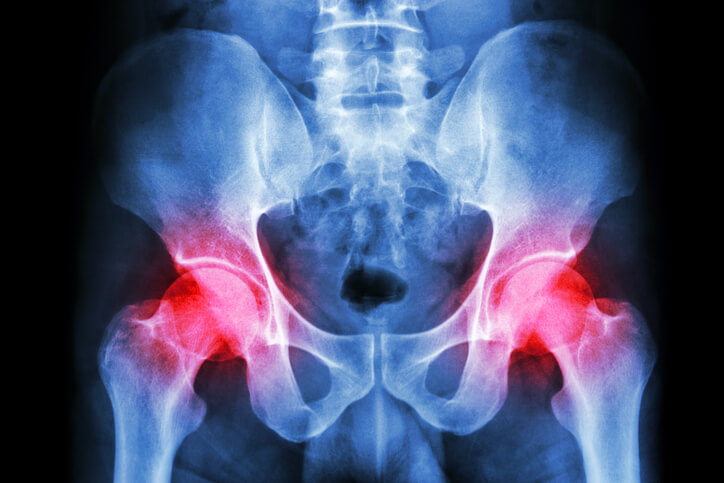

主な例として挙げられるのは、骨盤を支えている骨に異常やズレが生じる仙腸関節障害や、股関節を構成している軟骨がすり減ってしまう変形性股関節症などがあります。

まず、骨盤の底部には中央に仙骨、その仙骨を囲うように周りに腸骨という骨があり、骨盤を根元から支えています。

仙腸関節障害とは、その仙骨と腸骨の間にある関節に不具合が生じる病気のことです。